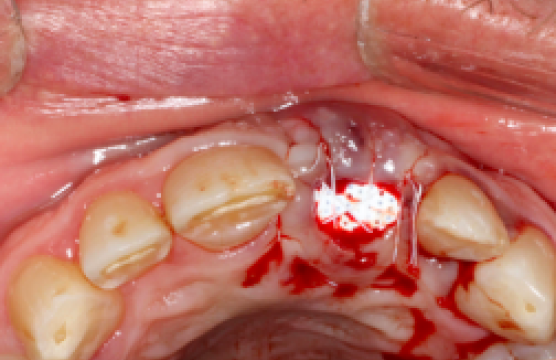

Surgical Site Preparation Process

Socket Preservation for implant

Before

Extraction of 21

After

Socket Graft of 21:

Surgical Site Preparation Process

Socket Preservation for implant

Before

Extraction of 21

After

Socket Graft of 21: 3 Months